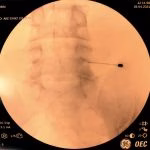

- Rizotomia percutânea lombar

- Implante de neuroestimulador medular